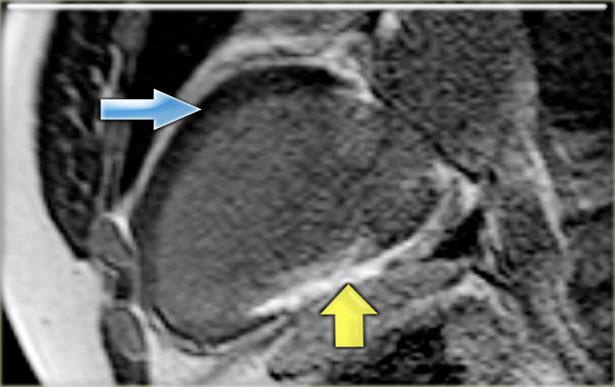

Bên trái là ảnh ngấm thuốc muộn trục dài của cùng bệnh nhân.

Lưu ý các điểm sau:

- Ngấm thuốc xuyên thành thành dưới, có thể chẩn đoán là nhồi máu cũ (mũi tên vàng)

-

Không có ngấm thuốc ở thành trước giảm vận động (mũi tên xanh).

Do đó có thể kết luận rằng đây có khả năng là kết quả của ngủ đông cơ tim.

Sau can thiệp nong mạch vành qua da (PTCA), chức năng thành trước đã cải thiện.

Phân suất tống máu cải thiện từ 17% lên 49%.